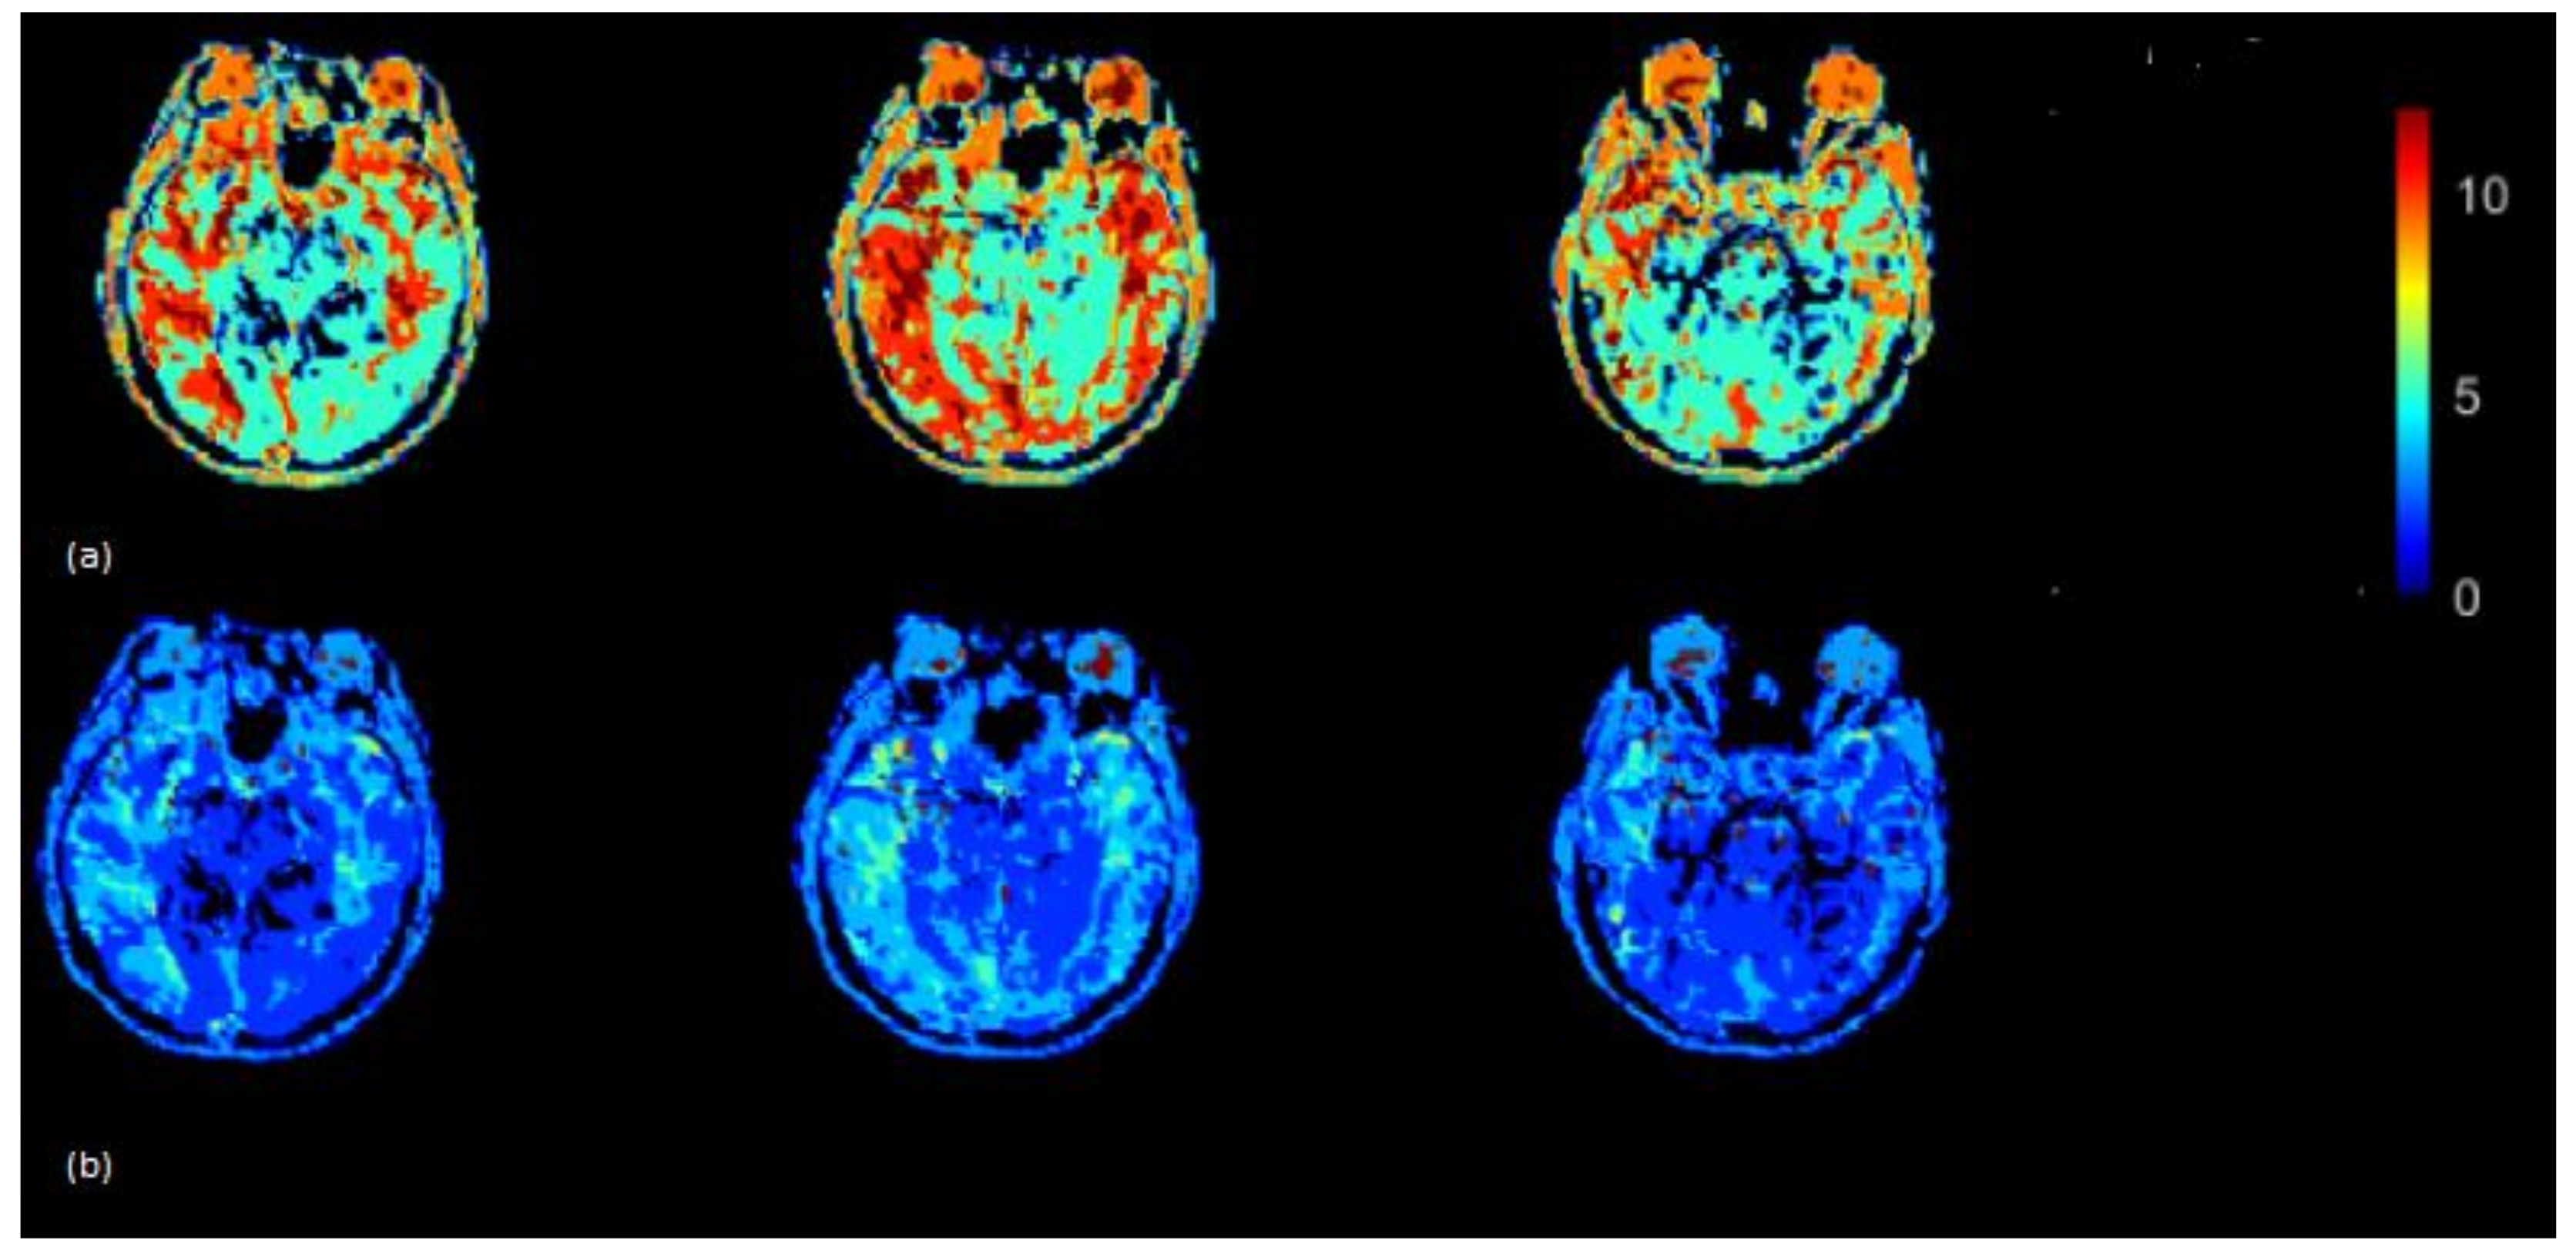

The CBF brain map was generated in the absence of scaling of AIF as well as by using the VOF rescaling approaches (Figure 5). In some cases, relative to the CBF map generated by using non-rescaled AIF, the CBF map generated by rescaled AIF approaches showed increased CBF values on the slices in the left and right hemispheres (red color) (visible in Figure 5). From Equations (5) and (6), it follows that the ratio of scaled and unscaled CBF values should be the scaling factor k. The images of the ratio of scaled and unscaled maps are expected to show the factor k for every voxel (Figure 5c). The mean CBF values, based on all 15 subjects using non-rescaled (AIF ROI width = 5 voxels) and VOF approach, were 43.98 and 61.16 mL/100g/min, respectively. The mean CBF values for AIF-rescaled and peak scaled approach were 57.10 and 47.10 mL/100g/min, respectively. At individual level, all the fifteen patients in this study did not follow similar pattern of underestimated CBF values due to the PVE. This has been demonstrated by studying the association of increasing degree of the PVE with deviation of CBF (Supplementary Material, Figure S1). To generalize, we need a larger dataset to conclude whether the scaling corrects the underestimation of CBF, as this could vary patient to patient in a small cohort.

Figure 5.

(a) CBF (mL/100 g/min) map generated by using rescaled AIF (b) and non-rescaled AIF (bottom). CBF map generated using rescaled AIF represents increased CBF values in the shown axial brain slices. CBF maps from non-rescaled AIF display mostly all the ROIs with decreased blood flow which makes it difficult to locate the regions which actually have a decreased flow. CBF images derived using rescaled AIF display ROIs with increased flow (red color) which helps to segregate the regions with decreased blood flow. This may help clinicals to identify the infract regions as well as regions with decreased blood flow on visual brain CBF images. (c) Maps illustrating the ratio between CBF values derived from the scaled and the non-scaled AIF.